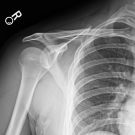

A 26-year-old right-handed man and student naval aviator presented with dull, achy, nonradiating pain at the sternoclavicular joint and inferior right sternocleidomastoid.

01/16/2019